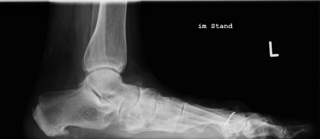

Die Ausbildung eines im Röntgenbild zu erkennenden Fersensporns ist für die Diagnose und Therapie der Plantarfasziitis nicht ausschlaggebend. Die Beschwerden können ohne Sporn bestehen, und Patienten mit einem Sporn können beschwerdefrei sein.

Der Fuß wird von vielen Muskeln, Sehnen und Bändern gestützt, um die Belastungen des Alltags zu meistern. Bei hoher Beanspruchung wie intensiver Sport, aber auch Berufe mit hauptsächlich stehender Tätigkeit und Übergewicht kann es zu einer Überlastung kommen. Ebenso können Fehlstellungen wie ein Hohlfuß oder ein Knick-/Senkfuß die Überlastung begünstigen. So ist ersteres oftmals mit einer eingeschränkten Beweglichkeit verbunden (Pronationsschwäche), während ein Knick-/Senkfuß mit einer Bedrängung eines Nervens durch eine kompensatorische Größenzunahme eines Muskels einhergehen kann (sog. Baxter-Nerv). Eine weitere häufige Ursache ist eine Verkürzung der Wadenmuskulatur.

Die Therapie der Plantarfasziitis ist nahezu immer konservativ. Hier ist meist eine über Monate andauernde Therapie notwendig. Abhängig von der vorliegenden Fehlstellung sollten spezielle Einlagen angefertigt werden. Ebenfalls sollten Dehnübungen der Wadenmuskulatur durchgeführt werden. Ebenfalls effektiv sind Übungen zur Aufdehnung der Fußsohle, die schon vor dem morgendlichen Aufstehen durchgeführt werden sollten. Da die Plantarfaszie durch die Mehrbelastung kleine Einrisse bekommt (sog. Mikroläsionen, die man sich vorstellen kann wie kleine Einkerbungen eines porösen Gummibandes, welches man in die Länge zieht), versucht der Körper dieses zur Vernarbung zu bringen, damit die dadurch bedingten Schmerzen abklingen. In manchen Fällen gelingt dieses nicht ausreichend, sodass Schmerzen lange anhalten können. Um dieses zu durchbrechen, ist die niedrigenergetische Stoßwellentherapie (ESWT) zu empfehlen. Diese Therapieform hilft, diese Mikroläsionen schneller abheilen zu lassen, wodurch die Schmerzen schneller abklingen. Studien haben die Wirksamkeit der Stoßwellentherapie nachgewiesen*, und seit 2019 übernehmen die gesetzlichen Krankenkassen die Kosten für 3 Anwendungen, sofern die Beschwerden länger als 6 Monate bestehen. In manchen Fällen sind dann die Beschwerden noch nicht vollständig abgeklungen, so dass eine Fortführung der ESWT als Eigenleistung möglich ist.